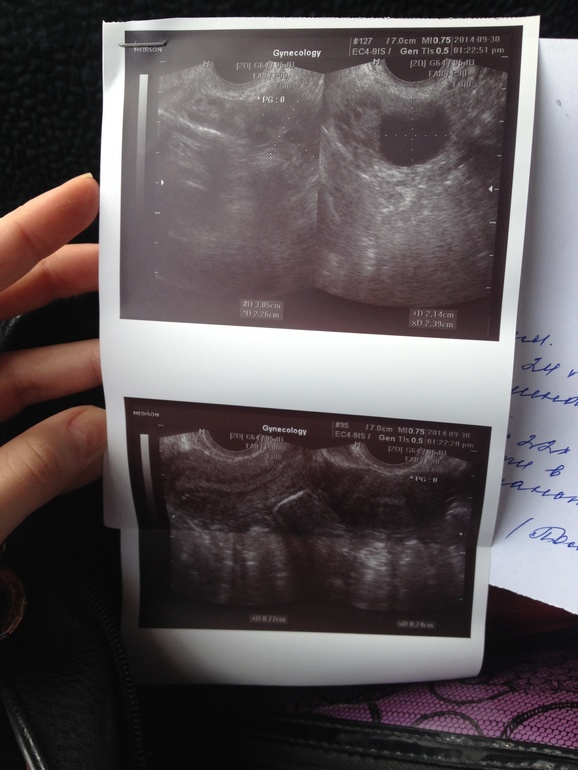

Милые девушки, посмотрите,пожалуйста мое узи. Что скажите? Меня узистка напугала, что левый яичник отдыхает, в правом фолликул, но он может и не лопнуть. Эндометрий очень тонкий, я спросила что может посоветовать,она ответила все к врачу. К нему надеюсь только в субботу попасть. А до субботы я же изведу себя.

Фолликул хороший. У меня такой же созрел, но мне моя Г назначила 5000ЕД укола ХГЧ и после него в течение 15 часов была О. Я её сама почувствовала. т.к. была резкая боль в правом яичнике и обильные выделения как Яичный белок. В вашем случае О должна до субботы произойти поэтому берите тесты на О и все будет хорошо!

буквально сутки до О осталось, эндик кто-то скажет, что на 1-2 мм маловат.. но и с таким везет. А второй яичник отдыхает — так и должно быть. Чаще всего они по очереди.. а у меня второй цикл левй работает, а правый чет и правда отдыхает.